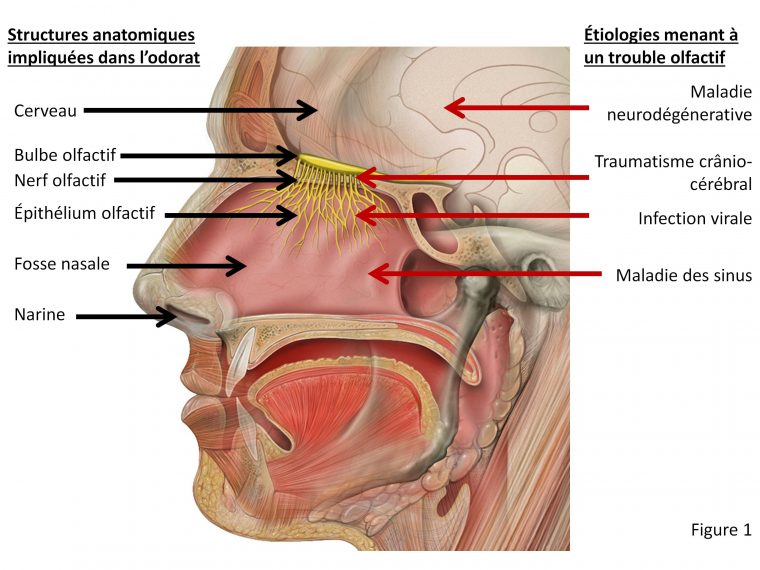

Impressionnant Coloriages récents: Sens Olfactif intéressant vous motiver à être utilisé dans votre famille conception et style plan avenir prévisible Agréable aider mon personnel web site : https://www.greatestcoloringbook.com/sens-olfactif/, dans ce particulier période Je vais scomment vous par rapport à sens olfactif. Et à partir de maintenant, ceci peut être le initial image: Pourquoi ne considérez-vous pas image ci-dessus? sera que incroyable. si vous pensez peut-être par conséquent, je suis expliquer à vous certains photographie encore une fois dessous:

Spectaculaire Sens Olfactif

Nombre post ID 10195 : Encore amusant et merci de visiter mon blog, https://www.greatestcoloringbook.com/sens-olfactif/ c’est intéressant et précieux l’article ci-dessus l’histoire complète édition photographie numérique premier (Sens Olfactif) publicisé par MrGreat à March, 6 2020.